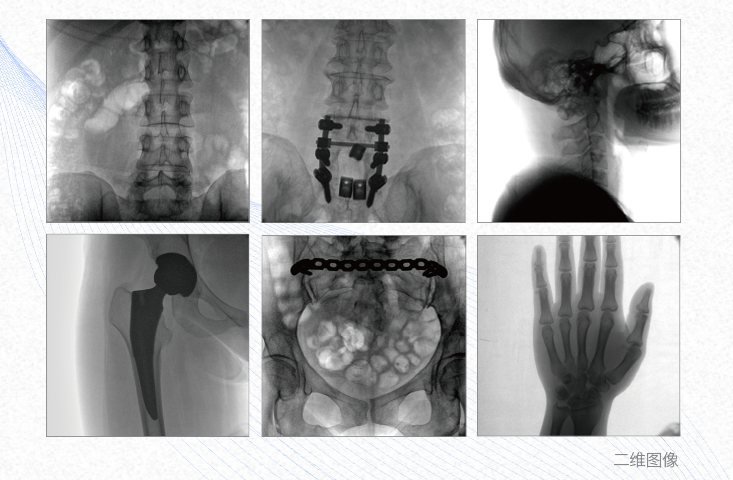

1、脊柱外科

有效重建復(fù)雜的脊柱三維模型,提供準(zhǔn)確的二維、三維圖像,提高螺釘植入的準(zhǔn)確性,縮短手術(shù)時(shí)間,減少并發(fā)癥的概率,降低輻射的攝入。

2、創(chuàng)傷外科

例如骨盆骨折內(nèi)固定術(shù),可術(shù)中三維重建髖臼關(guān)節(jié)面,準(zhǔn)確定位并植入螺釘,有效縮短螺釘植入的時(shí)間和透視暴露時(shí)間,減少術(shù)中及術(shù)后并發(fā)癥發(fā)生的概率。

3、關(guān)節(jié)外科

主要應(yīng)用于肩關(guān)節(jié)、肘關(guān)節(jié)、髖關(guān)節(jié)、膝關(guān)節(jié)的關(guān)節(jié)置換及解剖復(fù)位的定位。它可以準(zhǔn)確地置入假體,減少輻射時(shí)間,降低輻射劑量。

4、截骨矯形外科

例如治療先天性脊柱側(cè)后凸畸形,可有效引導(dǎo)術(shù)者植入后路螺釘并切除半錐體,達(dá)到滿意的截骨矯正效果。